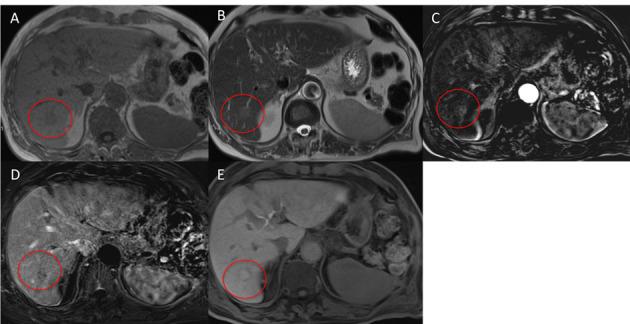

On computed tomography (CT) and magnetic resonance imaging (MRI), hepatocellular tumors are characterized based on typical imaging findings. However, hepatocellular adenoma, focal nodular hyperplasia, and hepatocellular carcinoma can show uncommon appearances at CT and MRI, which may lead to diagnostic challenges. When assessing focal hepatic lesions, radiologists need to be aware of these atypical imaging findings to avoid misdiagnoses that can alter the management plan. The purpose of this review is to illustrate a variety of pitfalls and atypical features of hepatocellular tumors that can lead to misinterpretations providing specific clues to the correct diagnoses.

在计算机断层扫描(CT)和磁共振成像(MRI)上,根据典型的影像学表现可对肝细胞肿瘤进行特征描述。然而,肝细胞腺瘤、局灶性结节性增生和肝细胞癌在 CT 和 MRI 上可能会出现不常见的表现,这可能导致诊断上的挑战。在评估局灶性肝病变时,放射科医生需要注意这些非典型的影像学表现,以避免误诊,误诊可能会改变治疗计划。本文旨在说明导致误诊的肝细胞肿瘤的各种陷阱和非典型特征,并提供正确诊断的具体线索。